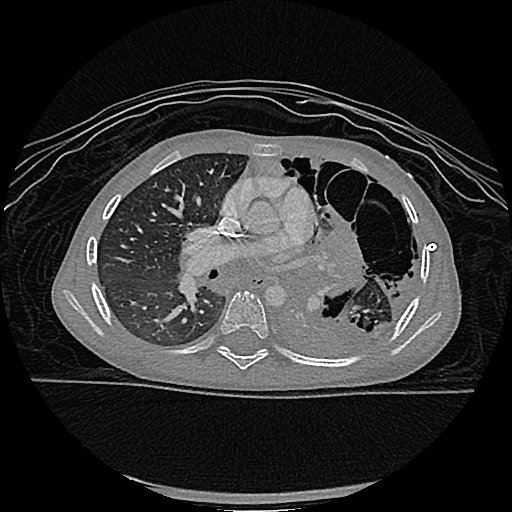

Hi all! So we all know about constrictive bronchiolitis, but can it happen in large airways? Below is post-SBRT obliterative bronchitis of LLL with secondary necrotizing granulomatous consolidation - awaiting stains but betting on NTM. A sort of (non) middle lobe syndrome!